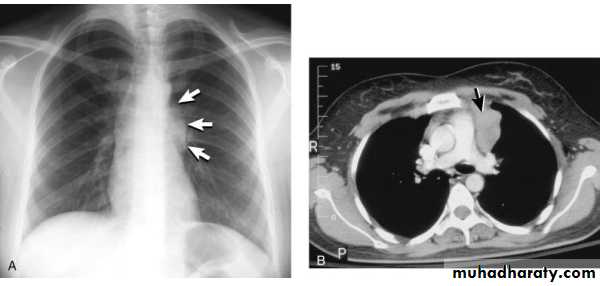

Tension pneumothorax.

On a posteroanterior chest x-ray (A), the left hemithorax is very dark or lucent because the left lung has collapsed completely (white arrows).

The tension pneumothorax can be identified because the mediastinal contents, including the heart, are shifted toward the right, and the left hemidiaphragm is flattened and depressed. A computed tomography scan done on a different patient with a tension pneumothorax (B) shows a completely collapsed right lung (arrows) and shift of the mediastinal contents to the left.